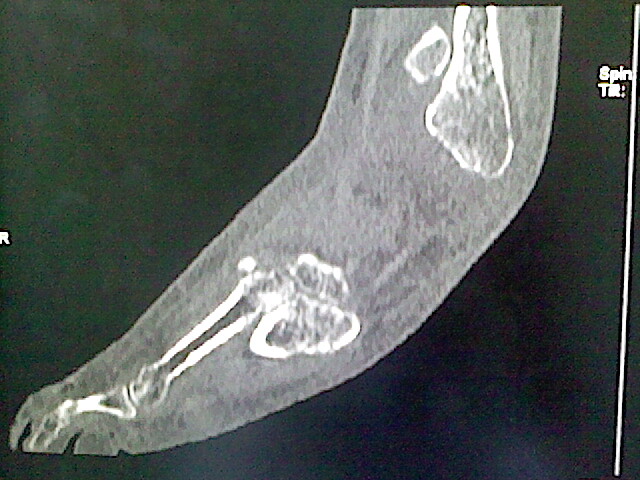

男,76岁,左小腿疼痛,不能站立

本例骨质改变主要表现为滑膜或韧带区的骨侵蚀融解(胫腓联合区骨质破坏无硬化边),距骨后部骨质破坏区有硬化边及死骨样改变.所以,本例考虑关节结核可能性大,绒毛膜结节性滑膜炎多发于中年,且极少见于膝髋以外的关节,骨质硬坏也以压陷吸收为主,有明显的硬化边,骨膜增生呈结节状(可以mr鉴别),所以本例暂除外.

另不除外可引起相似表现的其他炎症如布氏杆菌性关节炎等